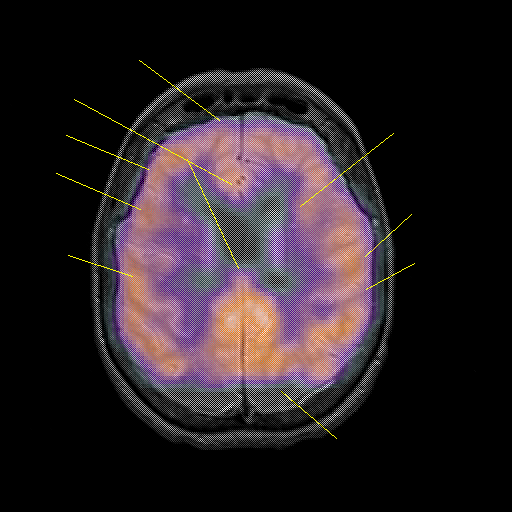

overlay : Slice 36

Slice 36

Unlabeled

Pointers

Labeled